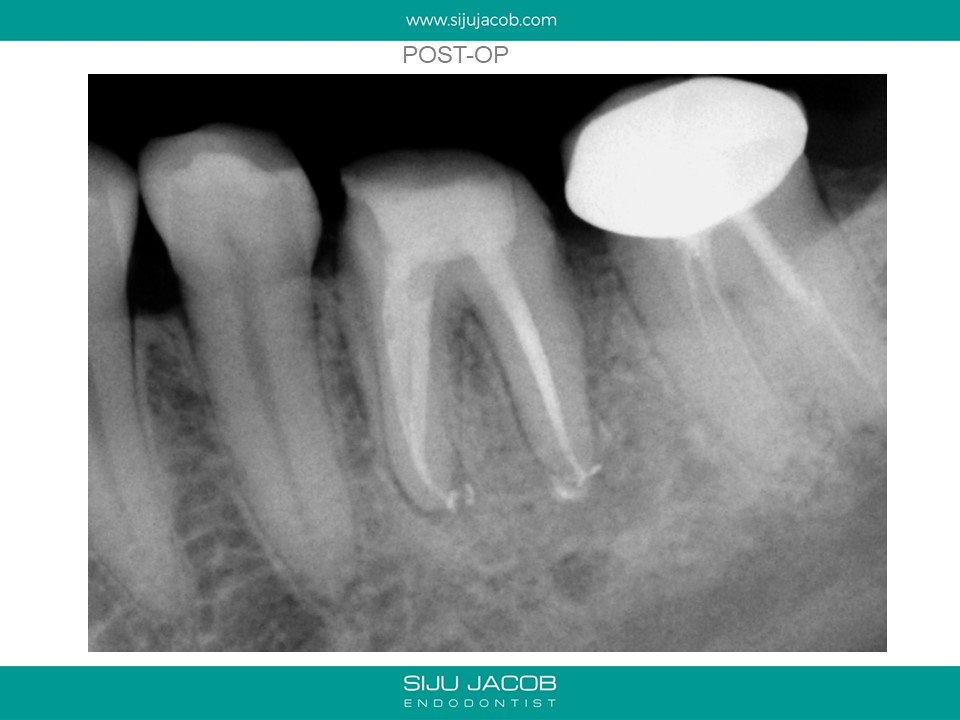

Written by Siju JacobApril 13, 2020 Molar Re-treat with large lesion This patient came with an acute abscess. Disassembly and re-treat with long term Caoh. One year recall shows healing. Share this: Share on X (Opens in new window) X Share on Facebook (Opens in new window) Facebook Like Loading... Related Leave a comment Cancel reply Δ